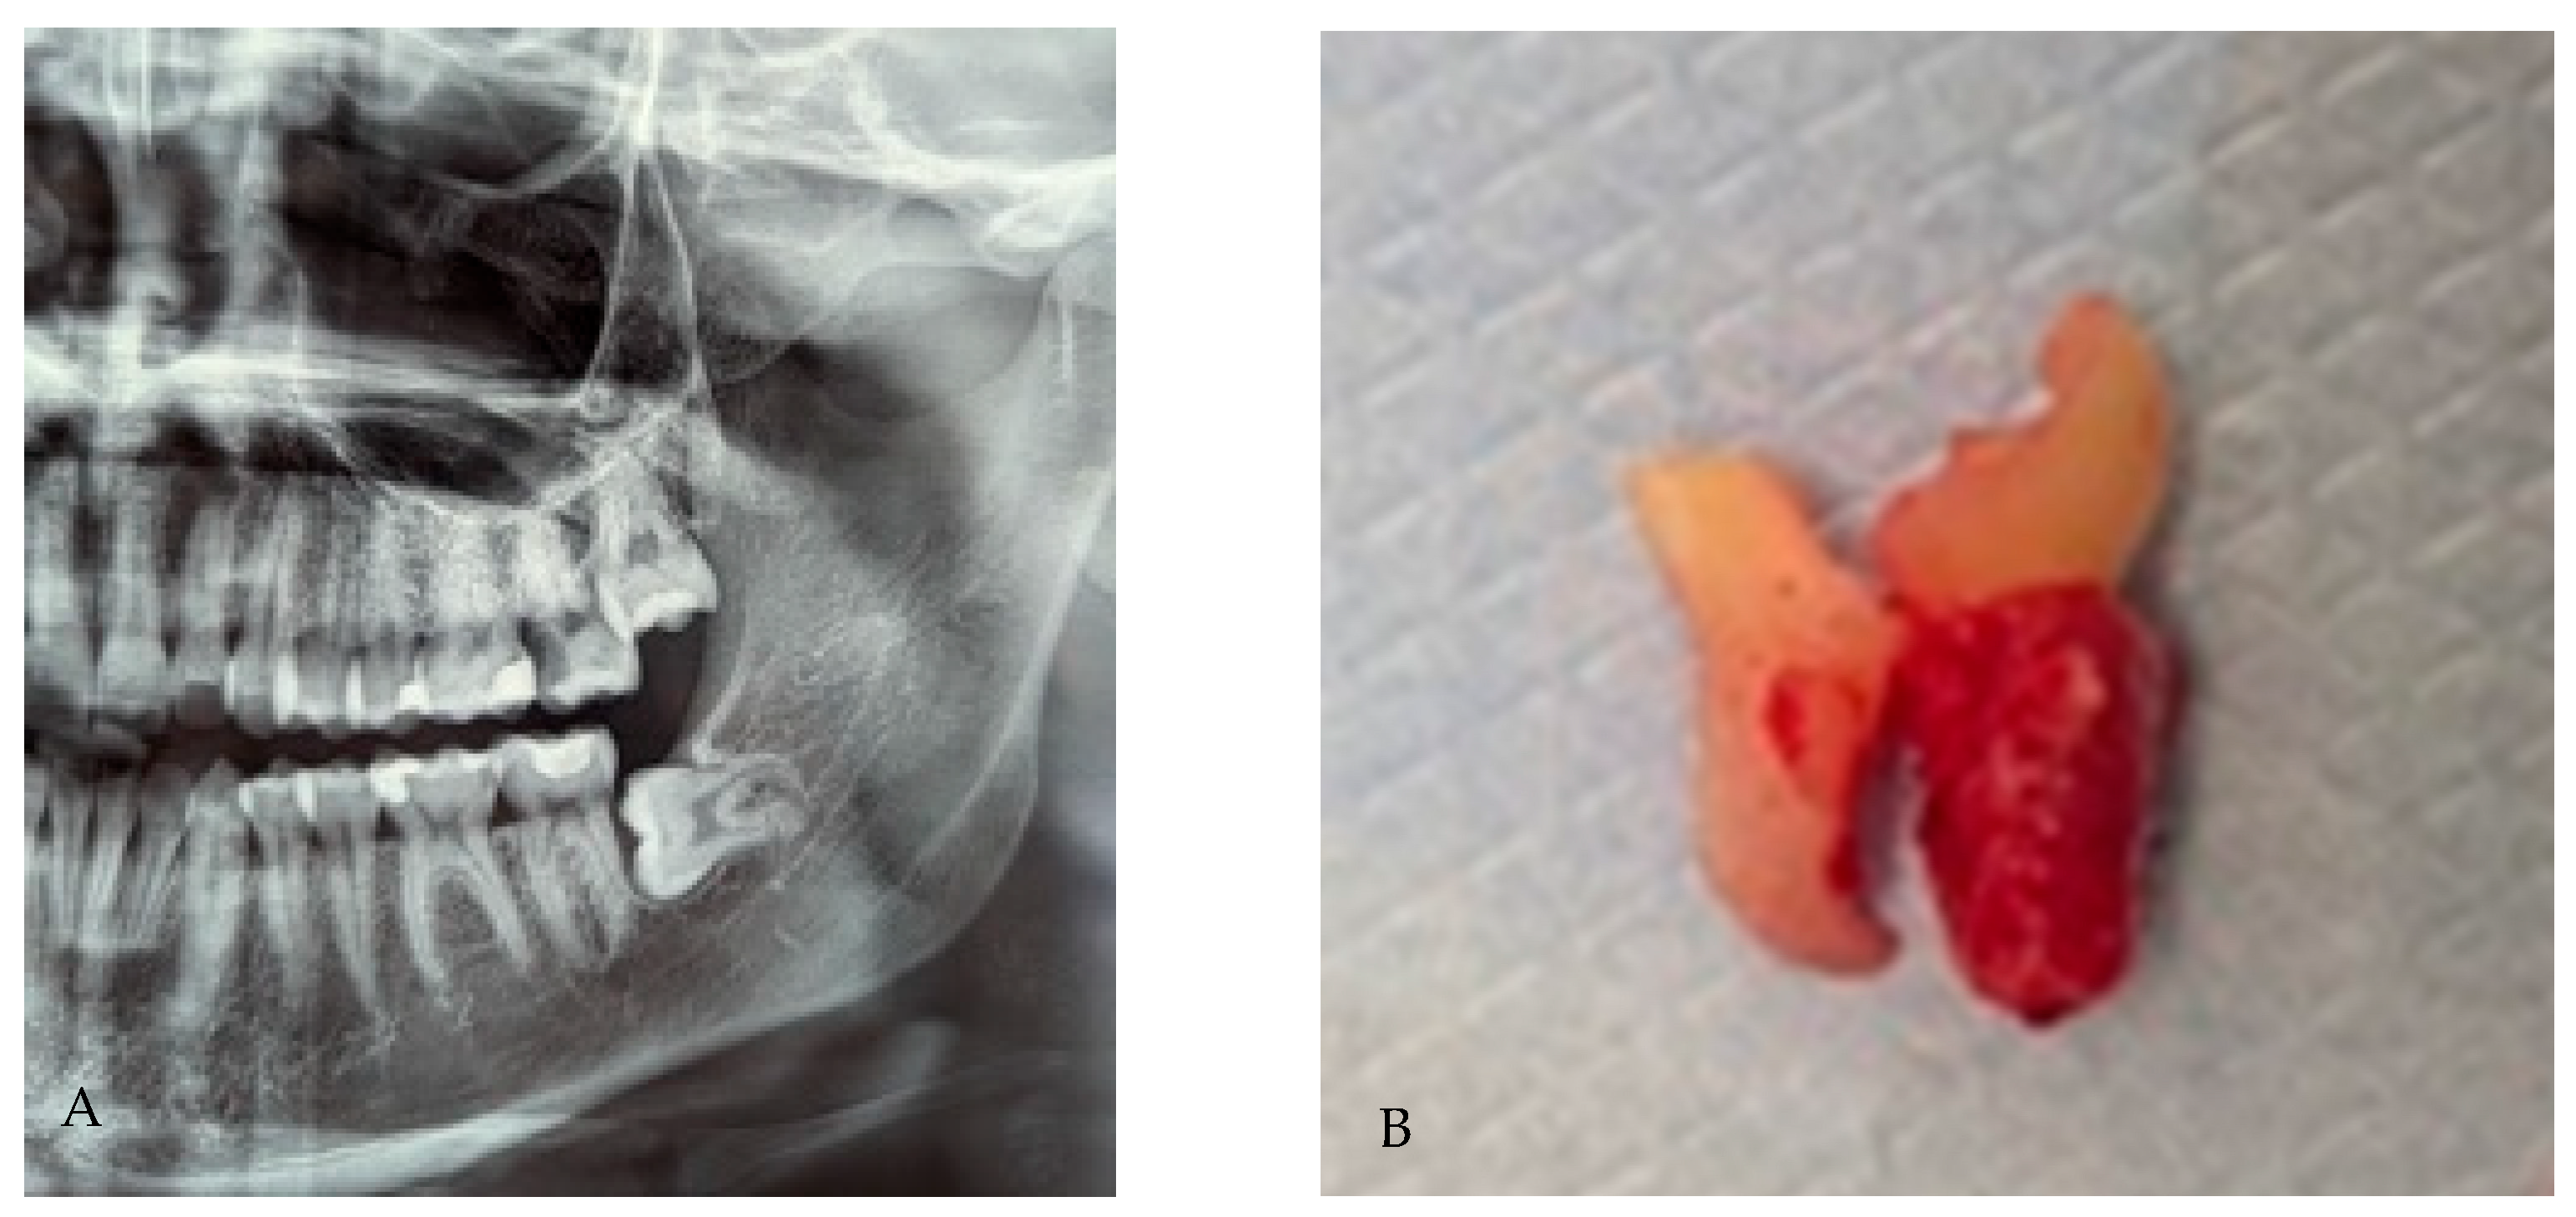

3.2. Radix Entomolaris

3.3. Radix Paramolaris